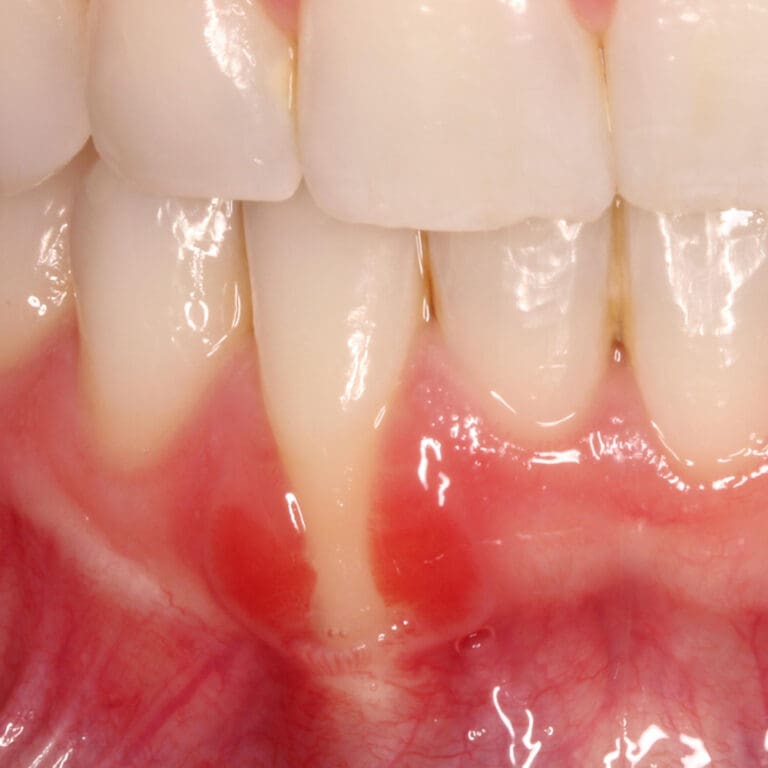

Gum Graft Healing Images . Here's what you can expect during and. Wondering about gum graft recovery timeline? Gum grafting covers exposed teeth roots and adds volume to your gum line, improving overall oral health. To repair the damage and prevent further dental problems, a gum tissue graft may be needed. How can you prevent gum. Explore our extensive gum grafting before and after gallery, showcasing procedures by our acclaimed periodontists. Achieve a healthy, natural smile. View 20 before and after gum graft photos, submitted by real doctors, to get an idea of the results patients have seen.

Wondering about gum graft recovery timeline? Gum grafting covers exposed teeth roots and adds volume to your gum line, improving overall oral health. How can you prevent gum. Here's what you can expect during and. To repair the damage and prevent further dental problems, a gum tissue graft may be needed. Explore our extensive gum grafting before and after gallery, showcasing procedures by our acclaimed periodontists. Achieve a healthy, natural smile. View 20 before and after gum graft photos, submitted by real doctors, to get an idea of the results patients have seen.